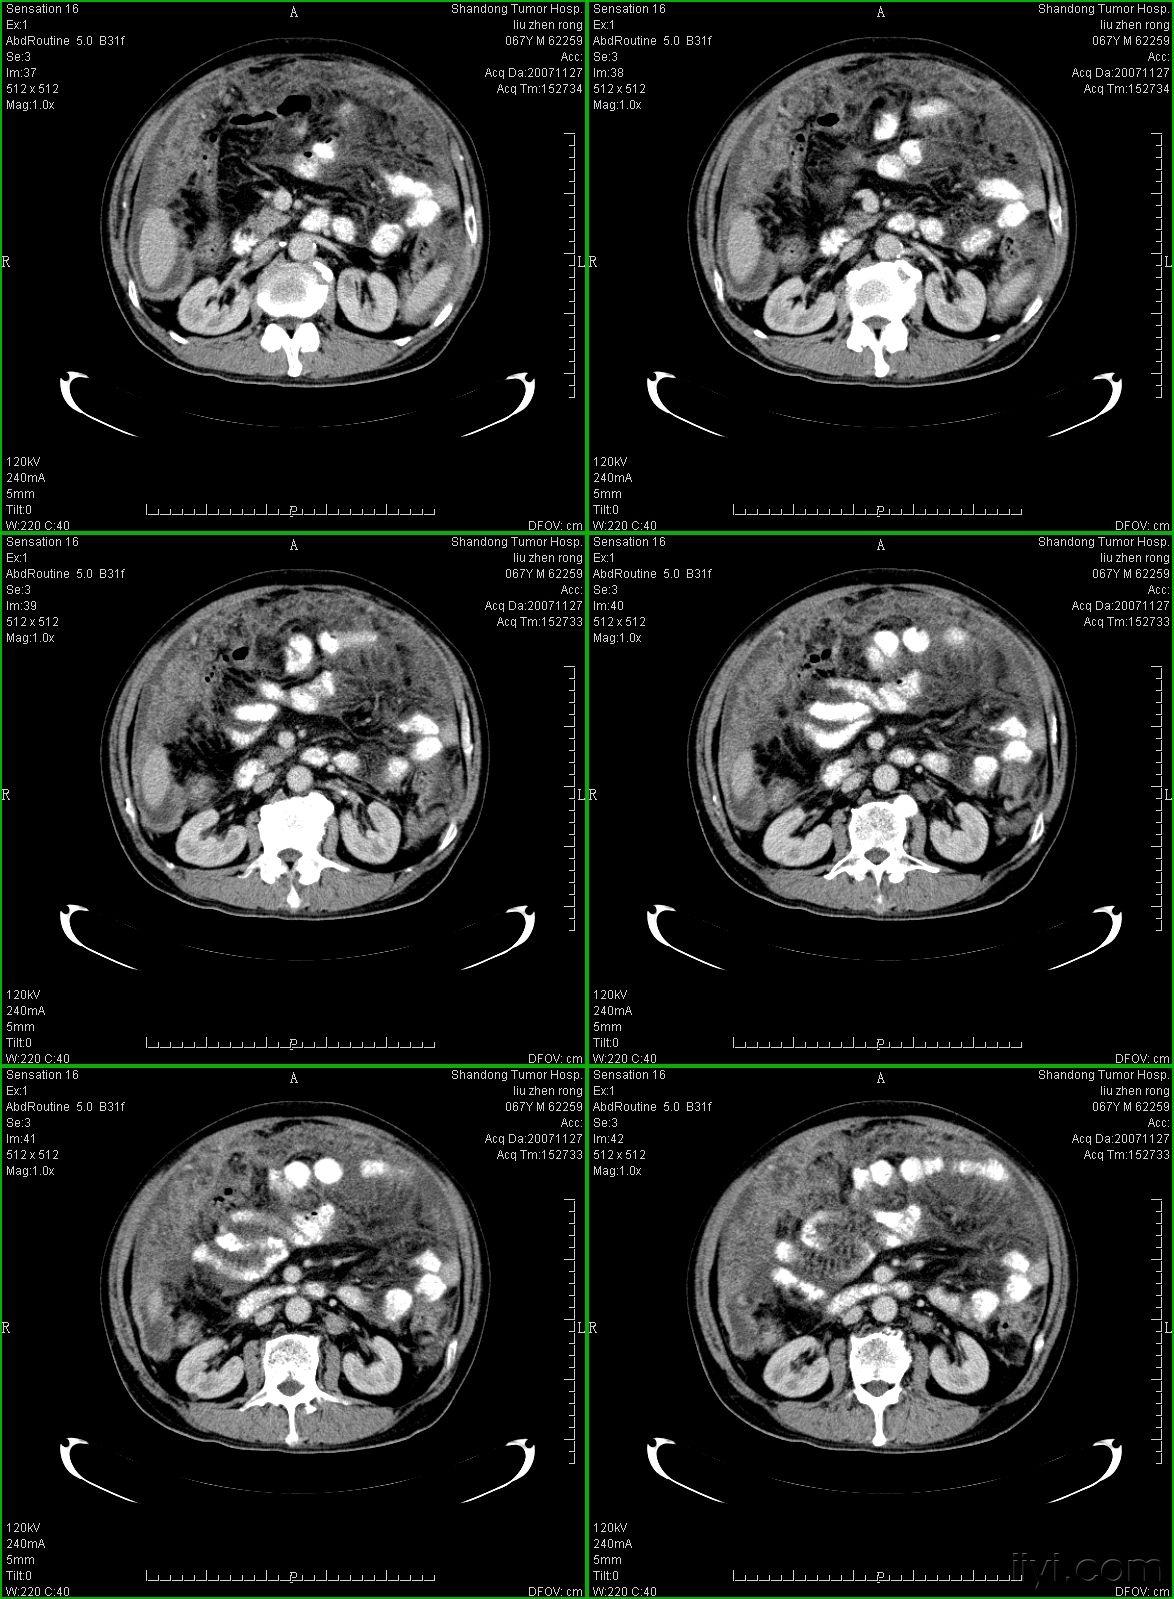

图2a大网膜成饼状(ct腹腔横断图象上出现肠曲被前面及两侧的肿瘤组织

典型的大网膜,肠系膜转移瘤,很经典

典型的大网膜肠系膜转移瘤很经典